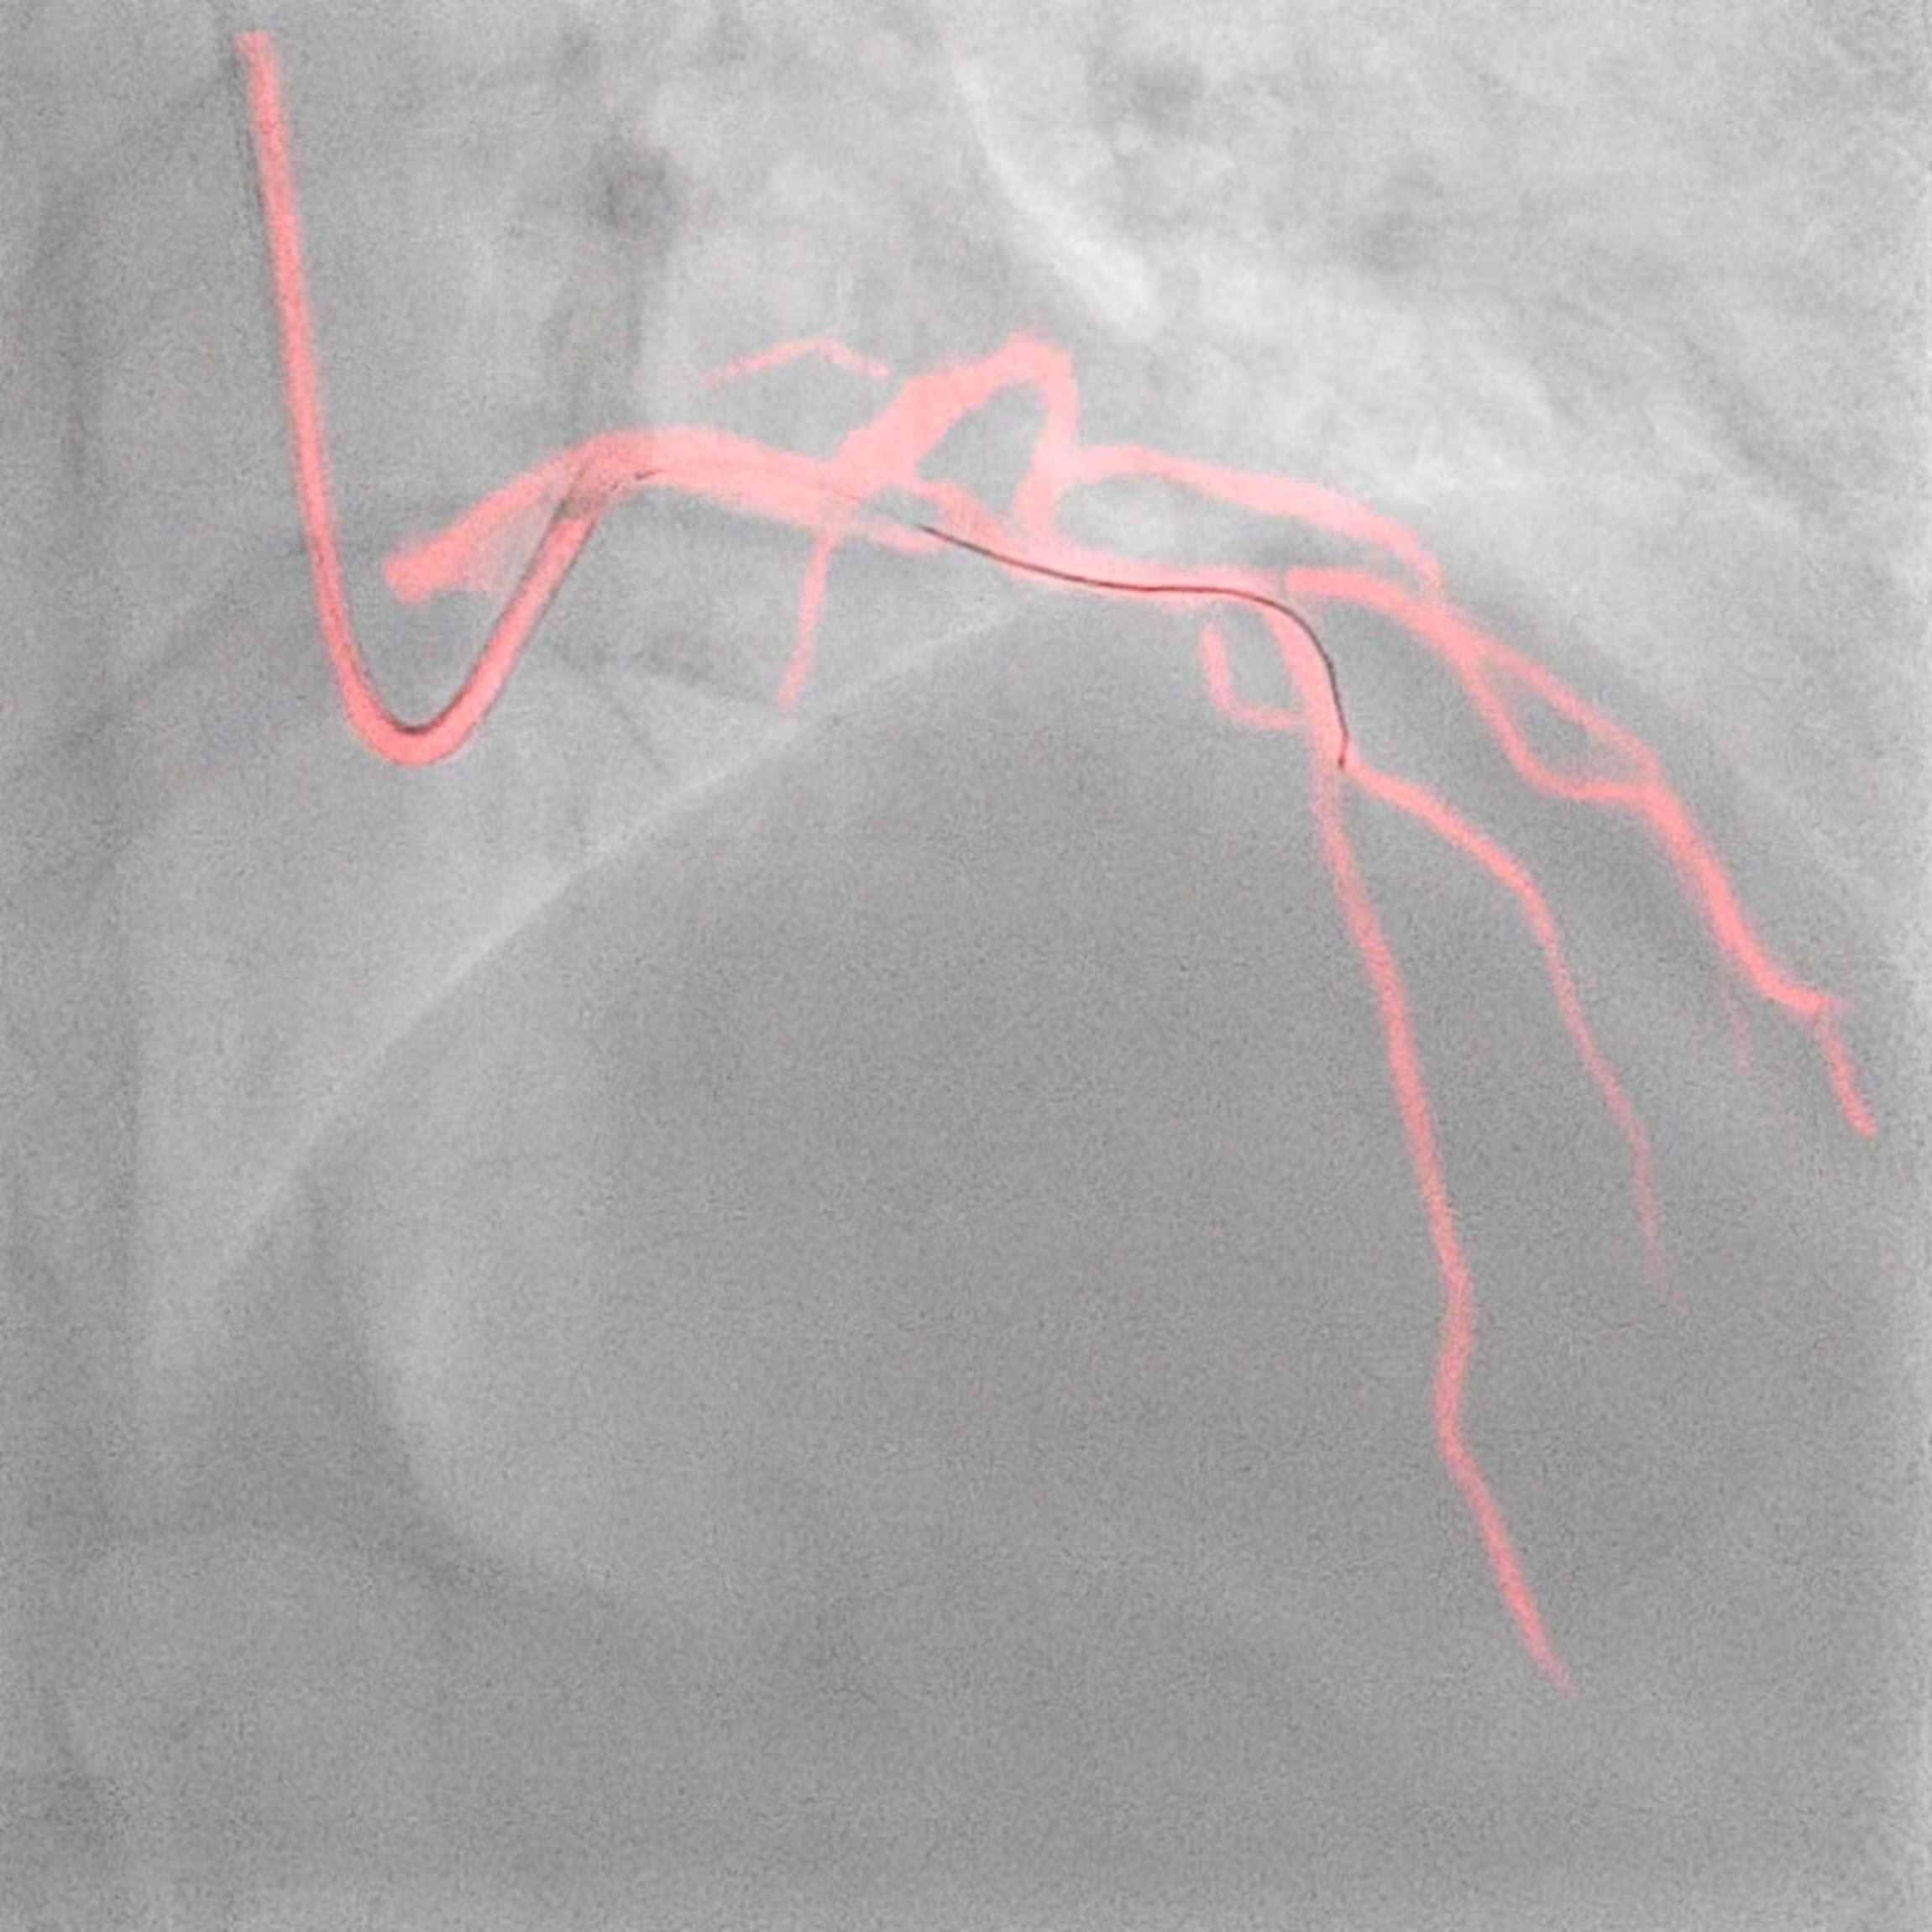

• Dynamic coronary roadmap for contrast reduction trial (DCR4Contrast): Prof. Javier Escaned, Head of the Interventional Cardiology Section at Hospital Clinico San Carlos, Madrid Spain, will present results from the DCR4Contrast trial, the largest-ever randomized controlled clinical trial on this topic, which investigated the ability of Philips Dynamic Coronary Roadmap (DCR) to reduce the total iodinated contrast media volumes administered during percutaneous coronary intervention (PCI) procedures, compared to PCI performed without DCR guidance. The late-breaker presentation will take place on Tuesday, May 16 at 12:00 to 13:30 (CET) in Room Maillot. Prof. Escaned will also present the results from the DCR4Contrast trial and is available for questions during the EuroPCR 2023 Press Conference taking place on Tuesday 16 May from 08:05 – 09:15am CET in the Press Room on Level 3.

Highlight innovations from Philips’ cardiology portfolio on display at EuroPCR include Philips Image Guided Therapy System – Azurion, Philips Interventional Applications Platform – IntraSight, next to visualization solutions such as Philips Precision Guidance System – SyncVision, Philips Dynamic Coronary Roadmap, live echo and live X-ray fusion tool – EchoNavigator, Pressure Guide Wire – OmniWire and its intravascular ultrasound (IVUS) catheters. Next to this, Philips will showcase atherectomy solutions, such as RX PTCA Scoring Balloon Catheter – AngioSculpt Evo, and its coronary laser atherectomy catheter – ELCA.

Live expert-led training sessions, symposiums and in-booth displays will give physicians and media insights into the latest developments in optimizing ULC-PCI procedures. Philips will also hold IVUS Simulation Sessions on recognizing different types of calcified plaque by intravascular ultrasound (IVUS) and optical coherence tomography. In the Philips Training Village visitors can learn more about how Philips solutions support interventionalists in minimizing the contrast load for the patient and physicians, and in performing interventional procedures with clarity and confidence using solutions such as IVUS, iFR, FFR and laser, improving cardiac care experiences for staff and patients.